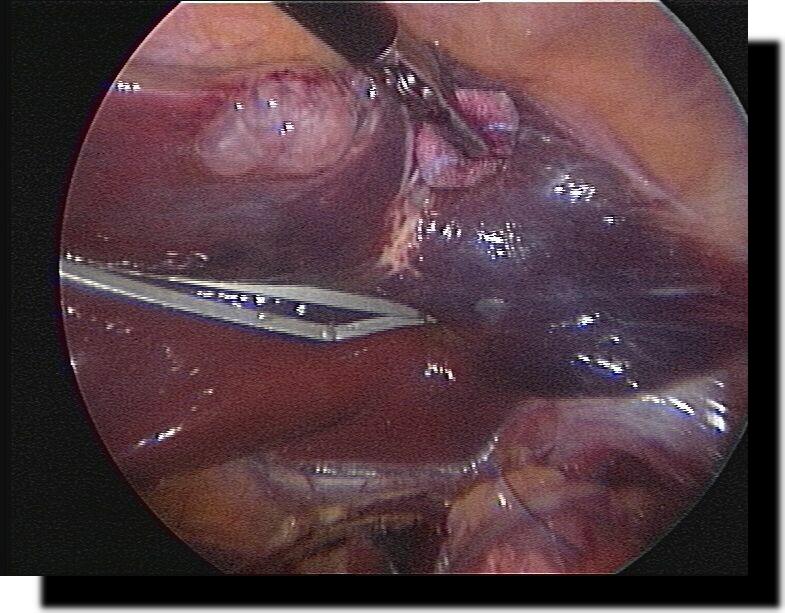

Akute eitrige Adnexitis